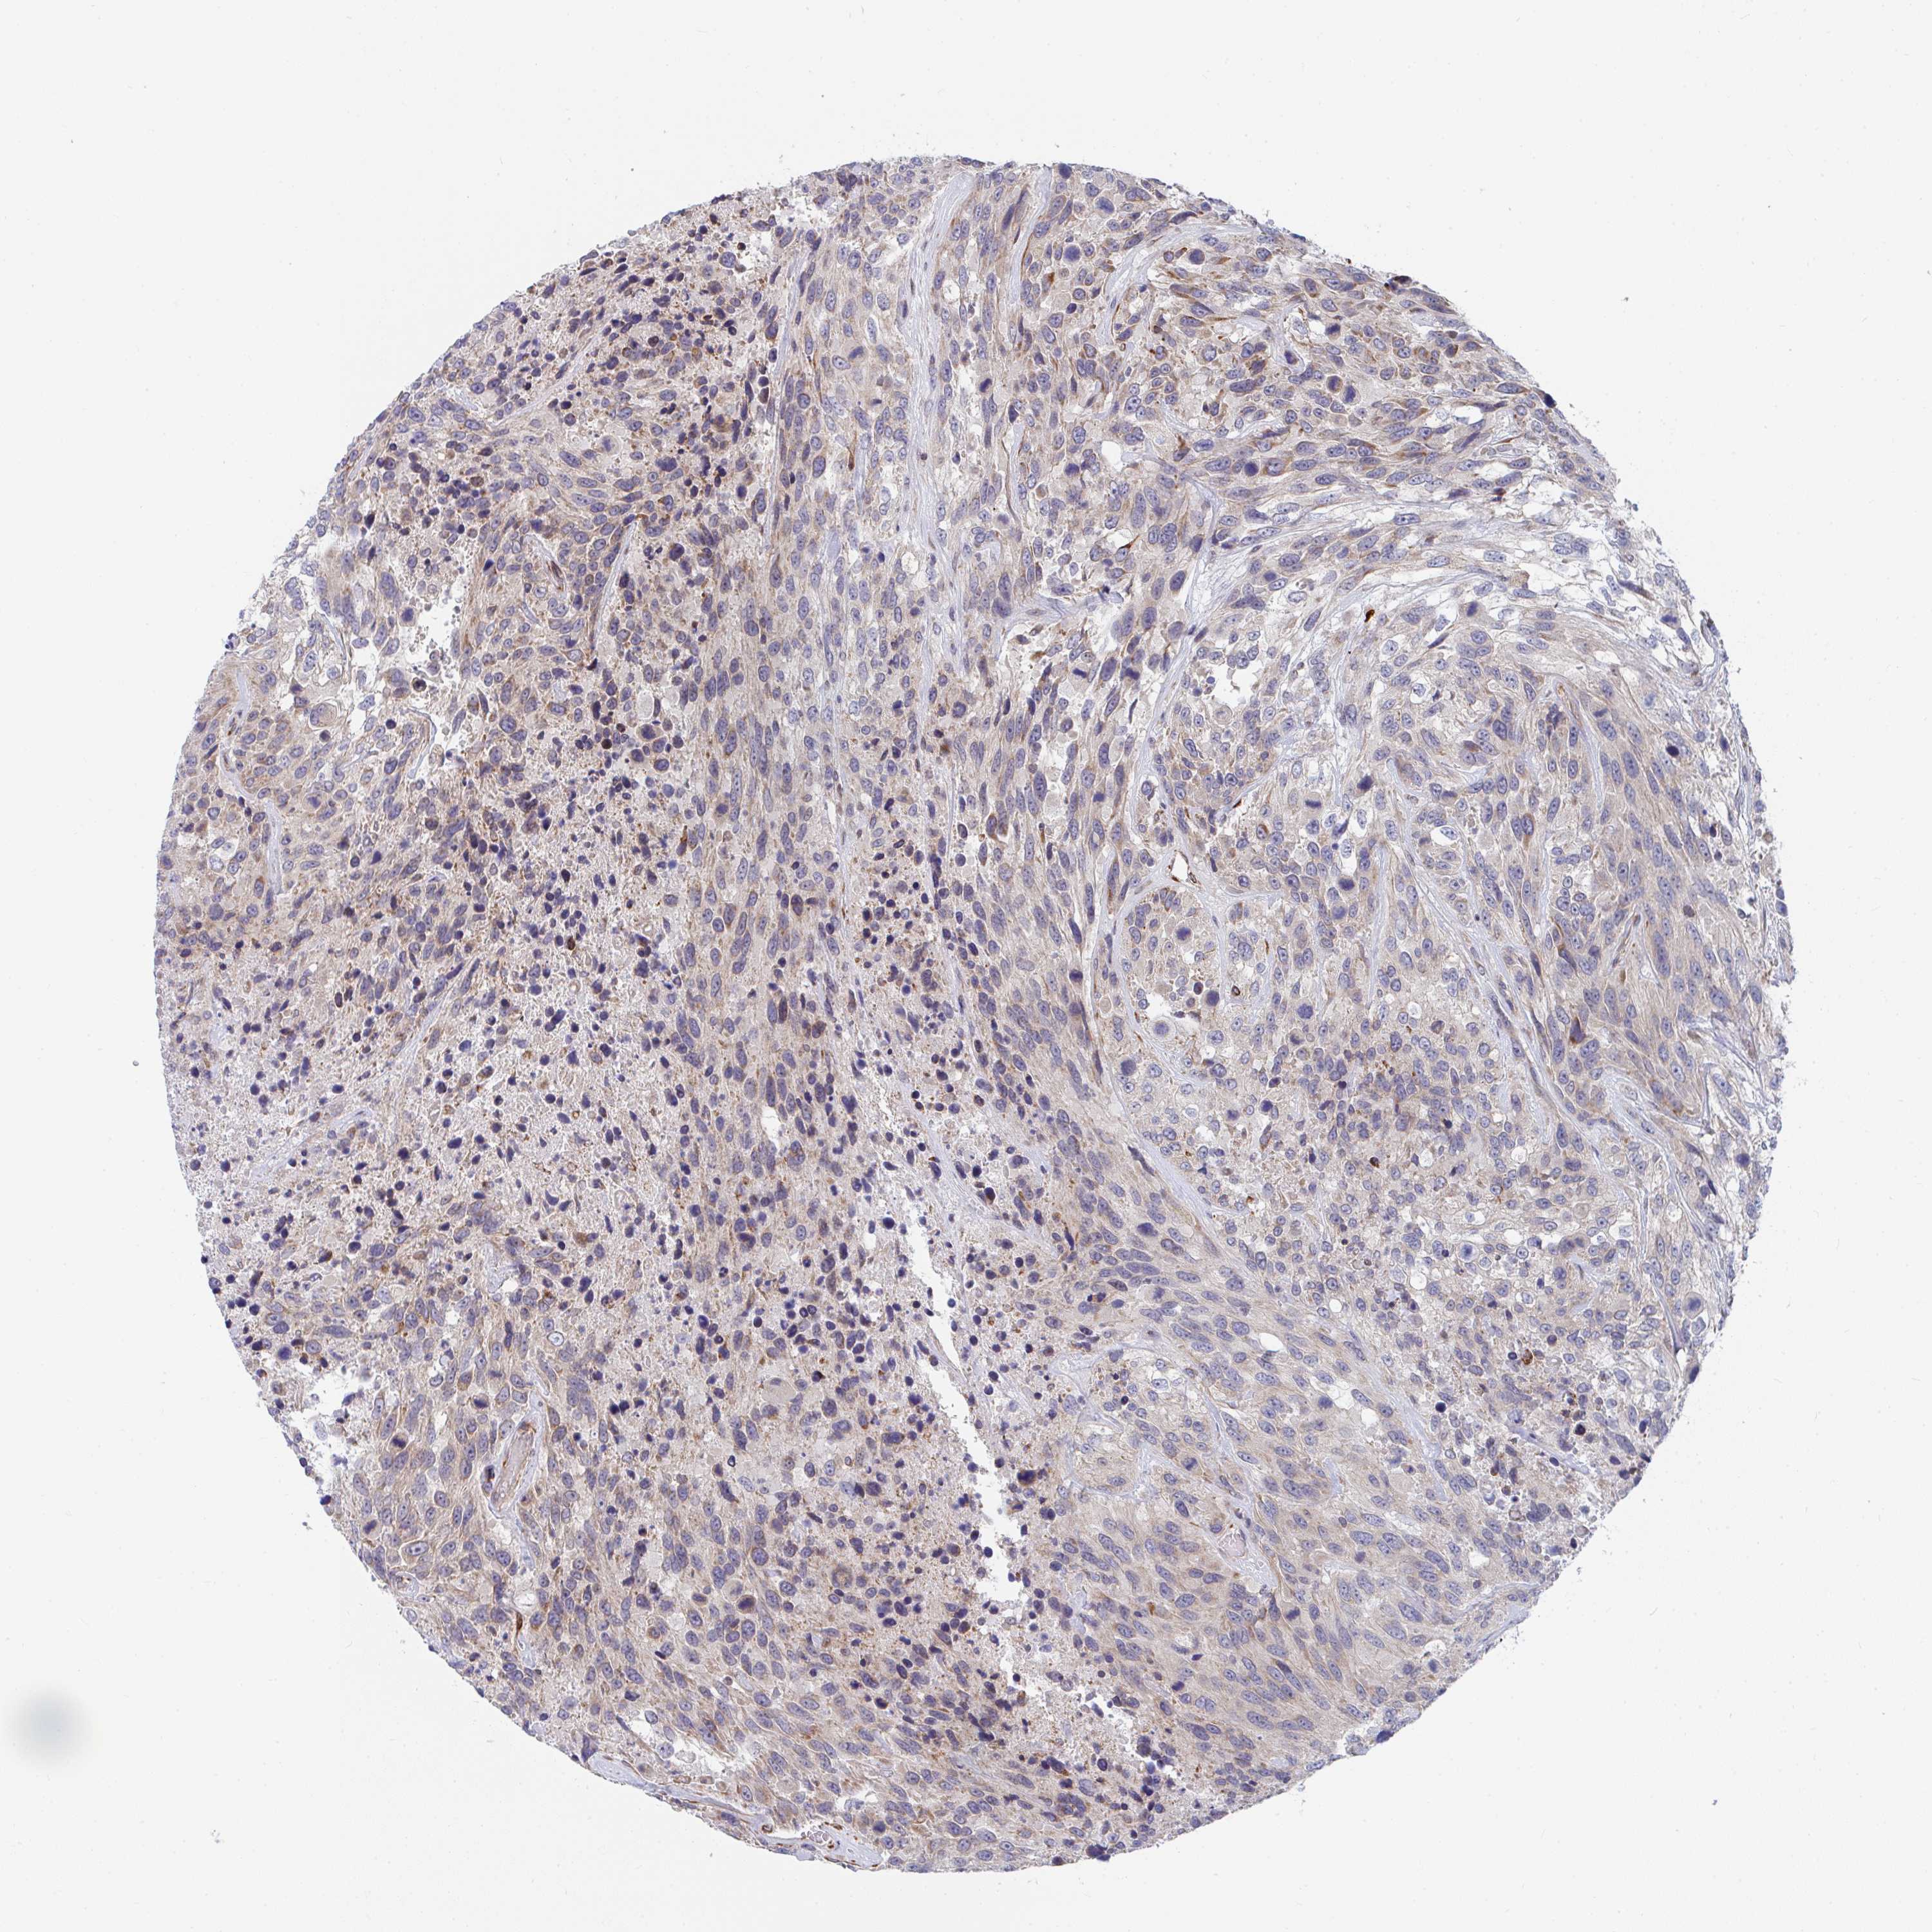

UROTHELIAL CANCER - Protein expressioni

A mouse-over function shows sample information and annotation data. Click on an image to view it in a full screen mode. Samples can be filtered based on level of antibody staining by selecting one or several of the following categories: high, medium, low and not detected. The assay and annotation is described here.

Note that samples used for immunohistochemistry by the Human Protein Atlas do not correspond to samples in the TCGA dataset.

Antibody stainingi

Antibody staining in the annotated cell types in the current human tissue is reported as not detected, low, medium, or high, based on conventional immunohistochemistry profiling in selected tissues. This score is based on the combination of the staining intensity and fraction of stained cells.

Each image is clickable and will lead to virtual microscopy that enables deeper exploration of all samples and also displays staining intensity scores, fraction scores and subcellular localization as well as patient and tissue information for each sample.

Antibody HPA054991

Antibody HPA058735

Urothelial carcinoma, High grade

Urothelial carcinoma, NOS

Urothelial carcinoma, Low grade